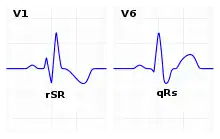

| ECG characteristics of a typical RBBB showing wide QRS complexes with a terminal R wave in lead V1 and a prolonged S wave in lead V6. | |

The criteria to diagnose a right bundle branch block on the electrocardiogram:

- The heart rhythm must originate above the ventricles (i.e., sinoatrial node, atria or atrioventricular node) to activate the conduction system at the correct point.

- The QRS duration must be more than 100 ms (incomplete block) or more than 120 ms (complete block).[8]

- There should be a terminal R wave in lead V1 (often called "R prime," and denoted by R, rR', rsR', rSR', or qR).

- There must be a prolonged S wave in leads I and V6 (sometimes referred to as a "slurred" S wave).

The T wave should be deflected opposite the terminal deflection of the QRS complex. This is known as appropriate T wave discordance with bundle branch block. A concordant T wave may suggest ischemia or myocardial infarction.